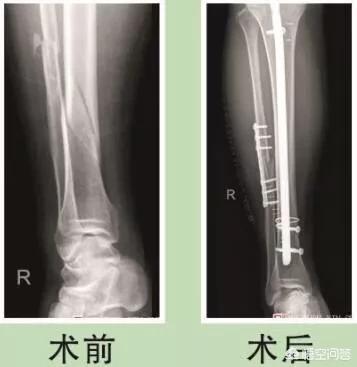

粉碎性骨折肯定比斜行骨折、裂隙性骨折、青枝骨折.....等单程性骨折要严重的多,因为他是高能量损伤,且骨折不稳定,手法复位困难,所以基本上都需要要手术固定治疗。

而粉碎性骨折需要做较大的手术。粉碎的碎骨块需要用骨钉,钢板,钢丝等固定好,再缝合,一般需要二次手术。

单从字面理解上来讲,粉碎性骨折就已经比较复杂了,但是不能理解为这种骨折就严重。骨折治疗的终极目的就是骨头在正确的位置上长上愈合。所以骨折的严重程度主要跟它的复位和愈合相关。

主要分为解剖复位和功能复位,简单的来说,解剖复位就是要求骨折对位严丝合缝,主要用于涉及关节面的骨折,比如踝关节骨折等;功能复位可以不要求片子上对位对线那么理想,只要满足正常的生物学力线即可,比如股骨干骨折等。因此,许多粉碎性骨折,如果不涉及到关节面的时候,其实并不那么严重,反而更好处理。